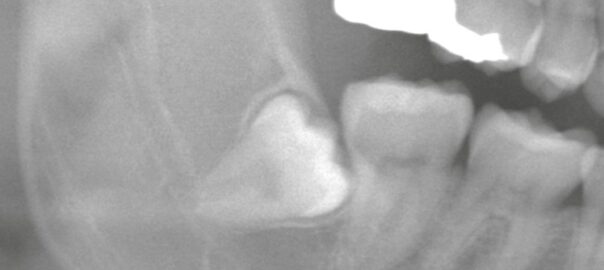

歯根が直角に湾曲した埋伏親知らず|2Dレントゲンでは見えないリスクとは?

こんにちは。東京都中央区銀座5丁目にある 【親知らず・顎関節症クリニック銀座(通称:オヤアゴクリニック)】です。 当院は以下の3つに特化した歯科クリニックです。 * 親知らずの抜歯 * 顎関節症の治療 * アスリートのた … 続きを読む 歯根が直角に湾曲した埋伏親知らず|2Dレントゲンでは見えないリスクとは?